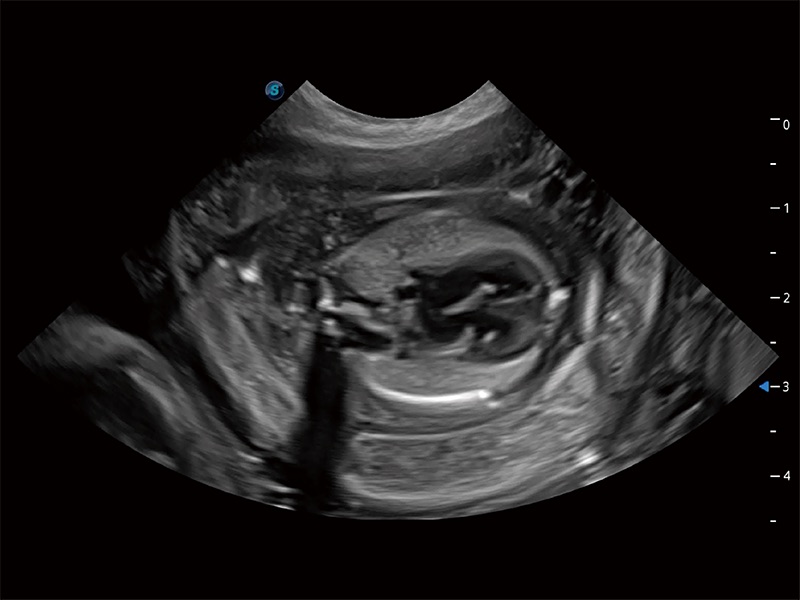

高性能和先進(jìn)的臨床應(yīng)用工具可以為動物醫(yī)生提供臨床信心。ProPet 80 搭載了先進(jìn)的腹部和淺表應(yīng)用工具,幫助醫(yī)生在日常臨床實(shí)踐中發(fā)揮前所未有的作用。

為精細(xì)結(jié)構(gòu)及組織邊緣提供高清晰度的圖像和更大的成像視野。幫助減輕醫(yī)生的用眼疲勞,快速精準(zhǔn)獲得測量的數(shù)據(jù)。